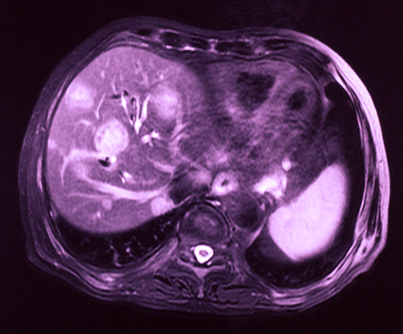

Researchers from the National Cancer Institute are predicting that the rate of hepatocellular carcinoma (HCC) in the United States will likely decrease by the year 2030.